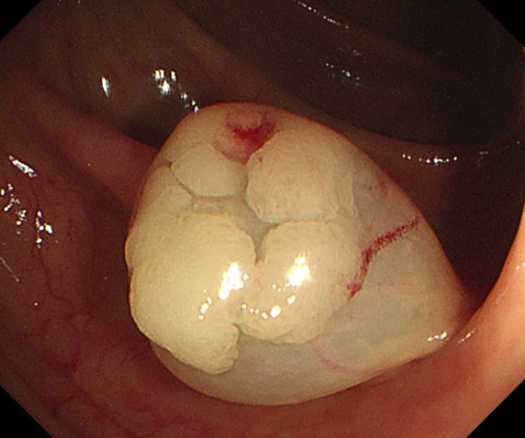

1) 대장내시경적 용종절제술 (Polypectomy)

대장내시경을 통해 용종을 발견하면, 내시경에 부착된 작은 루프를 사용하여 용종을 잘라내거나 태워 제거합니다.

이는 가장 흔한 치료 방법이며, 시술 후 용종은 암 여부를 판단하기 위해 조직 검사를 받게 됩니다.

2) 내시경 점막하 박리술 (Endoscopic Mucosal Resection, EMR)

크기가 큰 용종이나 초기 단계의 대장암인 경우 사용되며 이 방법은 용종 또는 암 조직과 그 주변의 일부 점막을 제거하여 조직 검사와 치료를 동시에 진행합니다.

대장 용종의 크기는 시간이 지나면서 점차 커지게 되며 용종이 암이 되기까지는 보통 수년이 걸립니다.

그러나 크기가 작은 용종임에도 암세포를 가지고 있는 경우도 있으며 선종성 용종의 1/3 정도는 3~5년에 걸쳐 암으로 진행합니다. 대장암의 95%는 대장 용종에서 발생하게 되므로 주위해야 합니다.